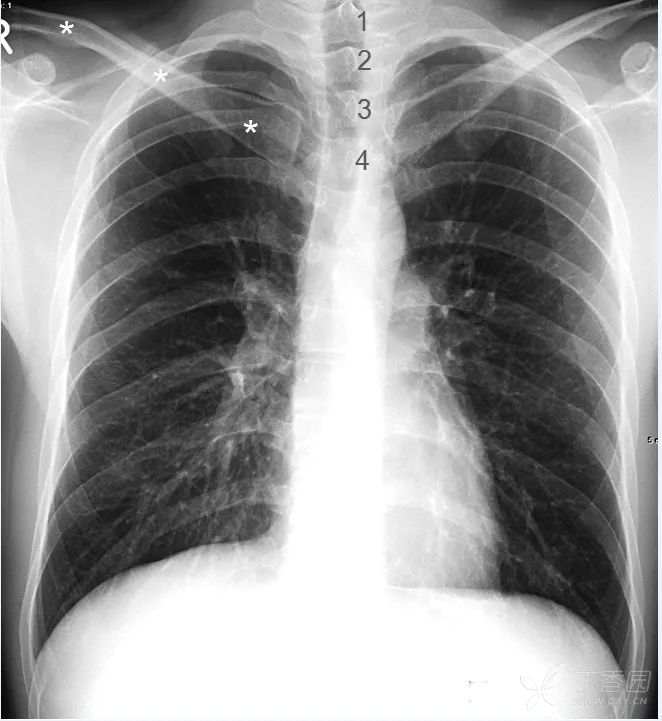

胸 椎 正位胸片上,胸椎和纵膈重叠。投照条件比较合适时,第1~4胸椎能够清晰识别,其余胸椎仅隐约可见。

锁 骨 两侧胸锁关节与胸部正中线等距,故可作为正位胸片投照位置是否端正的标准。

图中1~4分别标示第一到第四胸椎。其余胸椎隐约可见。白色星号标示右侧锁骨。